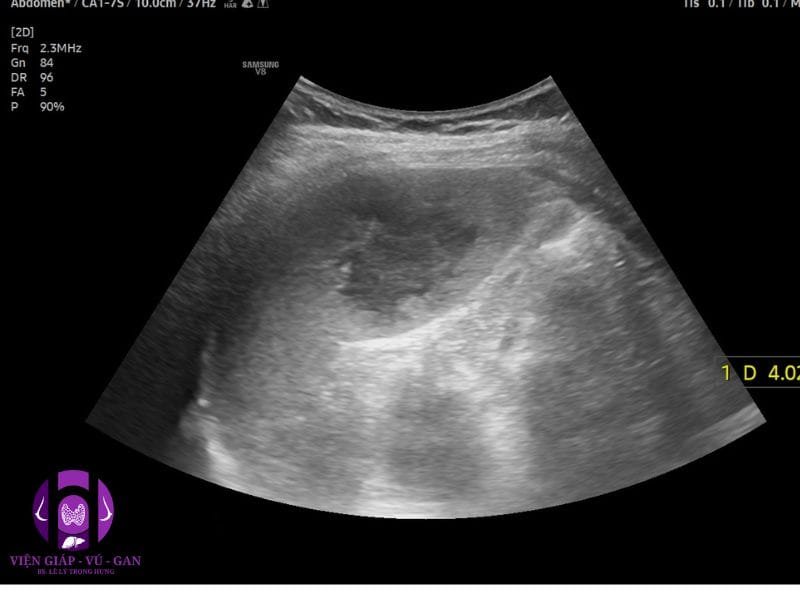

SIÊU ÂM BỤNG:

Lách: không to, cực dưới có khối echo dày, không đồng nhất, bờ đều, giới hạn rõ, kt# 40x30x25mm, doppler ghi nhận mạch máu phân bố rải rác ngoại vi và trung tâm.